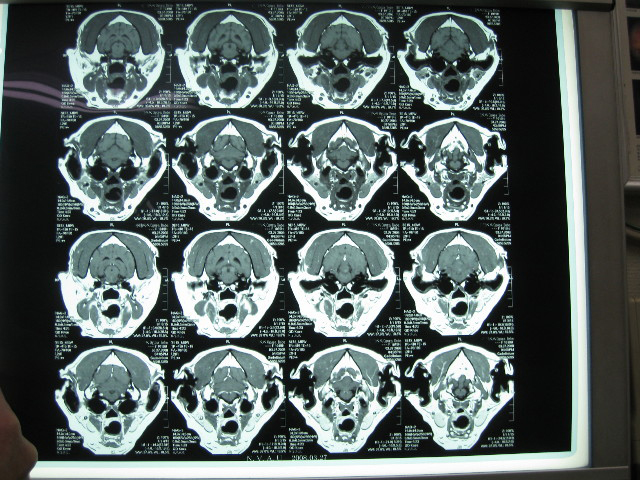

他の断面からみた小脳梗塞病変箇所。

こんな小さなポチで、こんなに大変な事になっちゃうんだよね....。

MRIのフィルムはね、お願いすると有料で現像してくれるの。

先生に診ていただくために全4枚を現像してもらってもらって帰ってきたんだよ。

ロールシャッハテストの絵みたいだよね。